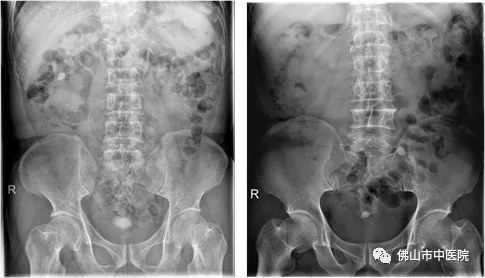

时光飞逝,20年过去了,罗女士逐渐出现排尿困难、尿频、尿急、尿痛,严重影响了日常生活。她开始慌张了,于是来到佛山市中医院就诊,行静脉泌尿系造影检查(IVP)被诊断出膀胱巨大结石。同时合并严重的感染,尿常规:白细胞(沉渣)(WBC)4893.2个/ul,医生建议必须在感染控制后,手术治疗。

经测量,这一结石体积约10.4厘米×9.1厘米×8.7厘米大小,一称竟重达280克。麦源表示,“膀胱结石常见直径在3厘米左右,这么巨大的结石而且长在正常女性身上,我还是第一次处理。”